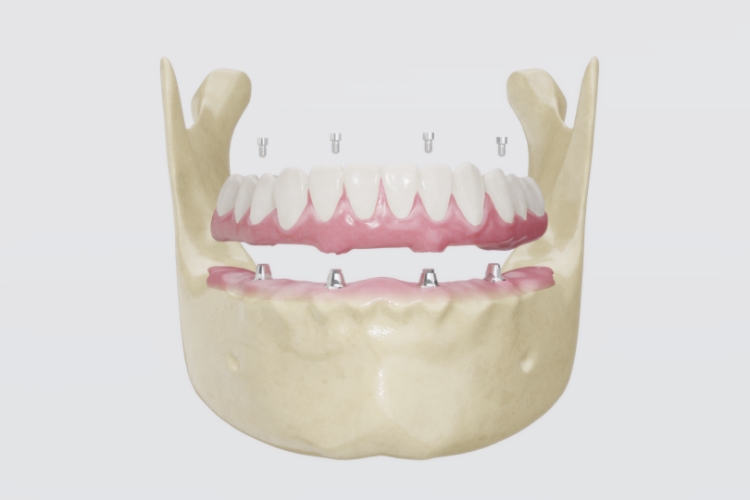

치아가 거의 없거나 전체를 상실한 경우, 최소 4~6개의 임플란트로 전체 치아를 고정하는

치료법입니다. 틀니와 달리 잇몸에 단단히 고정되어 자연치아와 같은 저작력을 회복할 수 있으며,

탈착의 불편함이 없습니다. 개인의 얼굴 비율과 치아 배열을 고려하여 제작하기 때문에

인공적인 느낌 없이 자연스러운 외관을 복원하며, 입술을 받쳐주는 힘이 개선되어 꺼진 볼이나

입 주변 주름이 완화되는 효과도 있습니다. 올바른 관리와 정기적인 검진을 통해 반영구적으로

사용 가능하며, 연결된 구조로 힘이 분산되어 오랜 기간 안정적인 기능을 유지할 수 있습니다.